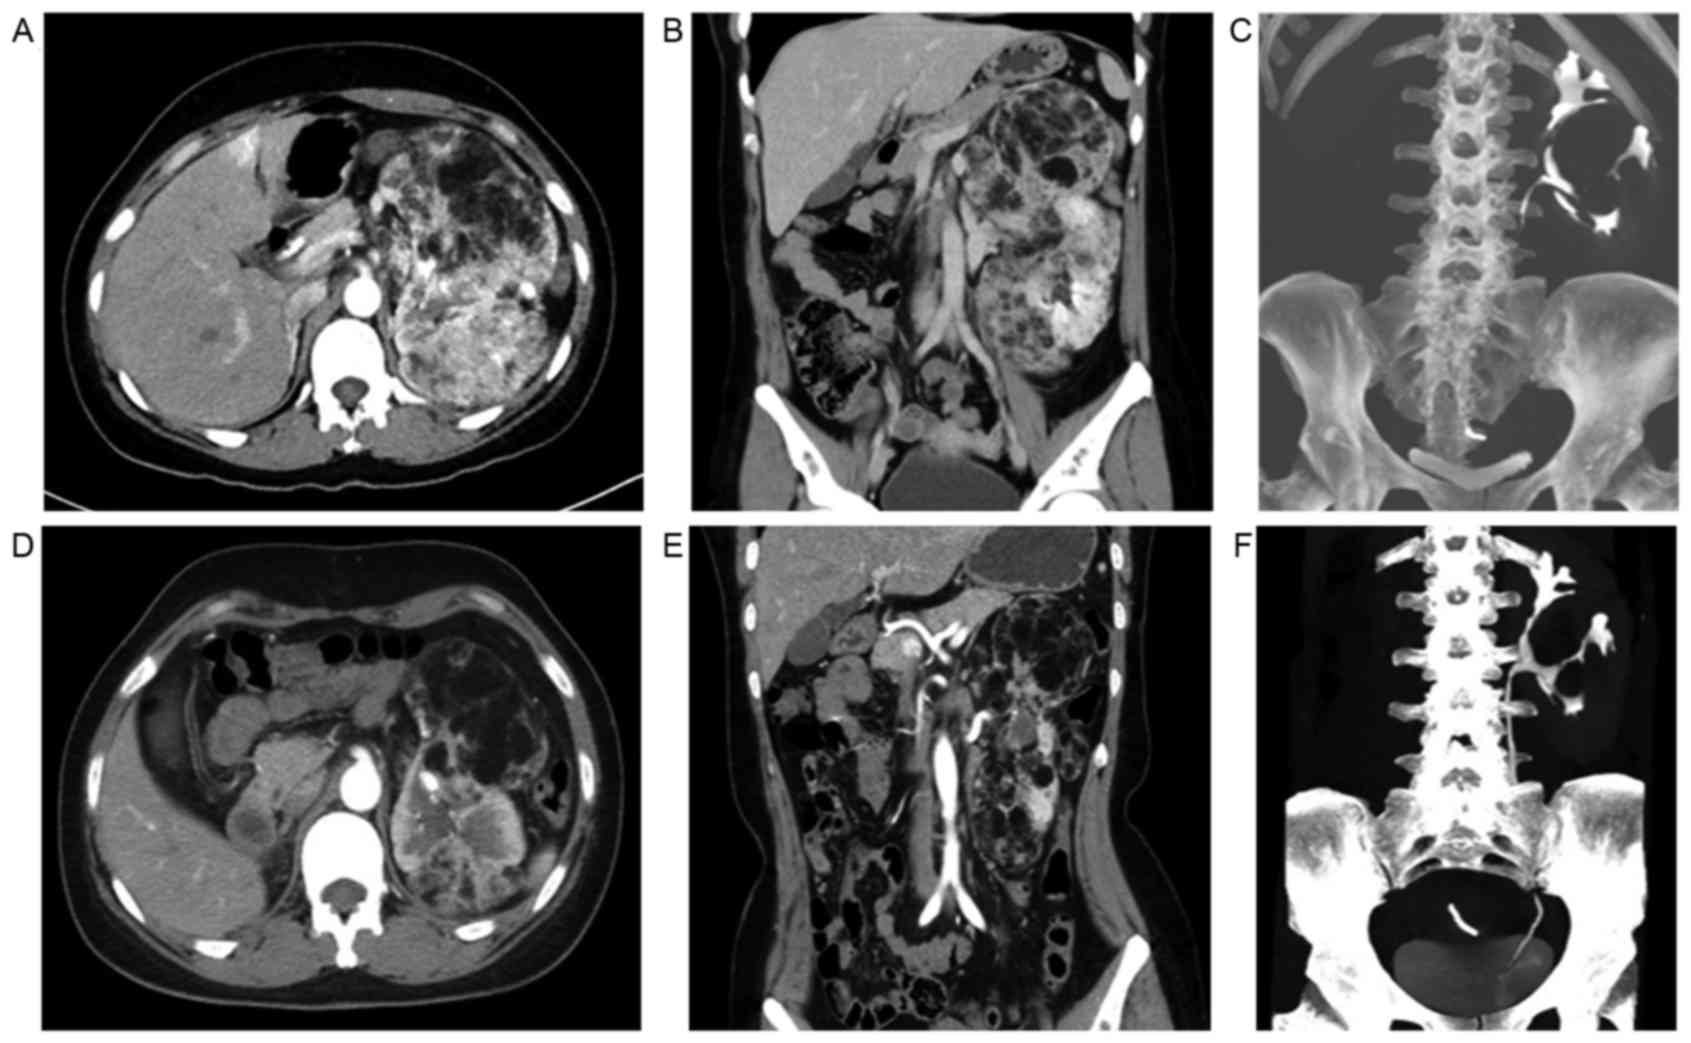

Everolimus treatment

Until the time of data collection, 2 of the TSC-RAML

patients had been treated with everolimus (10 mg/day, in a single

oral dose) for 3 months. The intermittent abdominal pain

disappeared completely, and the abdominal circumference of 1

patient was reduced by >3 cm compared with the initial data 3

months ago (measured while fasting in the morning). The maximum

diameter of the TSC-RAML decreased by 4.90 and 5.30 cm,

respectively, in the 2 patients, and the morphology of the renal

collecting system became more regular when compared with the

baseline data (Fig. 3). Changes to

(23). A sustained reduction in RAML

volume with continued everolimus treatment was also confirmed in

later results (24). In the present

study, following treatment with everolimus for 3 months, the

maximum diameter of TSC-RAML in the 2 patients decreased by 4.90

and 5.30 cm, respectively, the intermittent abdominal pain

disappeared completely and the facial angiofibromas improved.